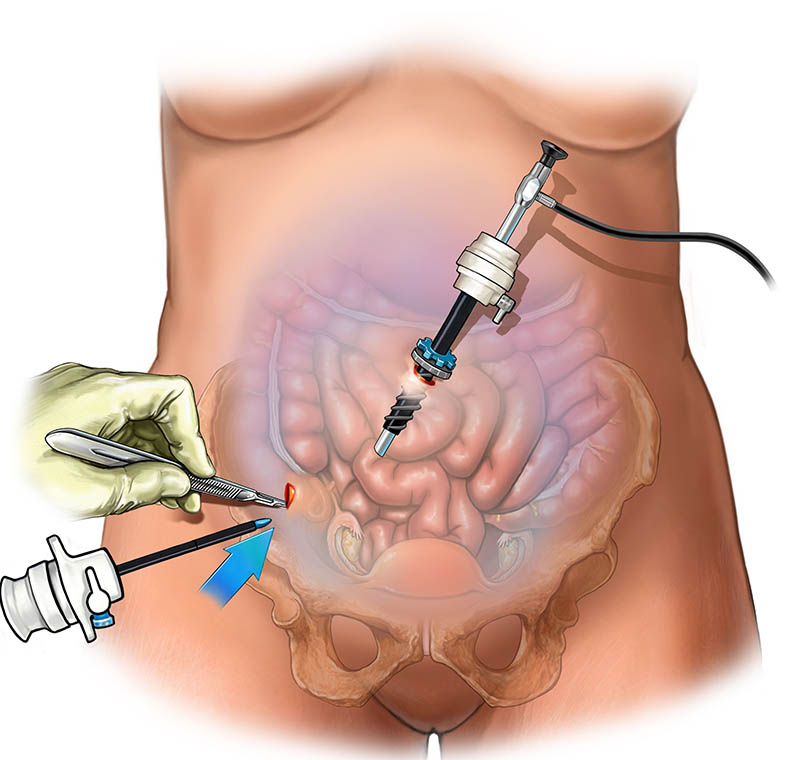

CSN Hospital (A unit of CSN Transparency Private Limited), was established in 2021 and in such a short span of time, it became one of the most respected hospitals in the State, and is also amongst the most preferred destinations for patients from several parts of the State. Our hospital specializes in cutting-edge medical procedures, spearheaded by experienced doctors who are skillfully supported by dedicated patient-care personnel.

Combining the best specialists and equipment to provide you nothing short of the best in healthcare